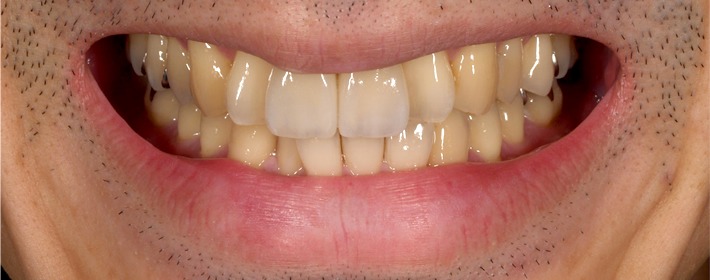

ファイナルレストレーション